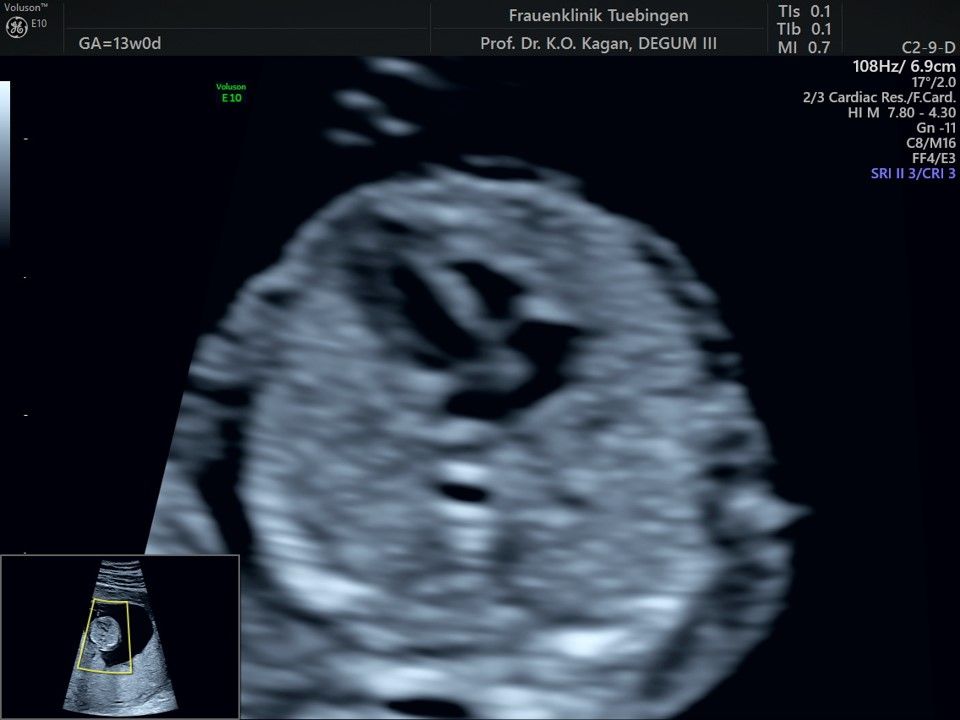

Im Rahmen des Ersttrimester-Screenings untersuchen wir die Organe des Feten mittels Ultraschall. Dabei machen wir auch gerne ein Bild für Sie.

Obwohl der Fet zu diesem Zeitpunkt erst zwischen 5 und 8cm groß ist, lassen sich bereits etwa die Hälfte aller schwerwiegenden Fehlbildungen erkennen bzw. ausschließen. Sollten wir eine Auffälligkeit sehen, werden wir mit Ihnen den Befund und das weitere Vorgehen ausführlich besprechen.

Das Ergebnis der Ultraschalluntersuchung ist wegweisend. Dabei wird der Fet vermessen, die Organe werden untersucht und die sonographischen Marker zur Risikoberechnung für Chromosomenstörungen werden beurteilt. Das sind: die Nackentransparenzdicke, Nasenbein sowie der Blutfluss in der rechten Herzhälfte und im Ductus venosus, einem Gefäß in der Leber des Feten.